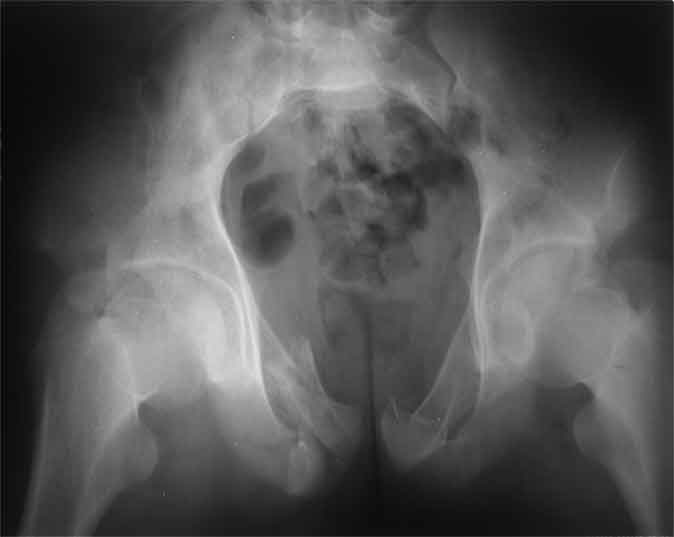

А чего там собственно таинственного? Билатеральное ротационно-нестабильное повреждение таза, перелом крестца в I зоне (по Denis)справа,частичное повреждение левого КПС, оскольчатые переломы лонной, седалищной костей справа (В3.2). Повреждение достаточно стабильное + молодой возраст+ сроки - оперативного лечения не требует.

Не смог разглядеть на представленных картинках частичное повреждение левого КП, повреждение Денис1-2 справа? 3Д реконструкции в инлет и боковой проекциях убедительно не демонстрируют типа повреждения задних отделов тазового кольца(справа боковая масса скомпремирована), Наверное, у тебя есть возможность оценить тип перелома крестца по прямой проекции 3Д.

по Pennal et al.- латеральное компрессионное повреждение тип В(ротационно-нестабильное (внутренняя ротация), вертикально стабильное)

по Tile classif. тип В2-1 - частично стабильное повреждение с неполным разрывом задней дуги.

По вертлуге- смог разглядеть только изолированный перелом передней колонны.

Насколько я понял из твоего письма, обращенного к анонимному vit, ты не видишь показаний к реконструкции перелома. Я бы взялся за реконструкцию(илео-ингвинальный доступ), хоть прошел и месяц после травмы: боковая 3Д показывает смещение нагрузочной зоны впадины, что однозначно будет способствовать разрушению хряща головки и впадины( особенно у 16 летнего пациента с ожидаемым высоким уровнем активности) + изменение геометрии впадины за счет неустраненного смещения фрагментов колонны (КТ, 3Д данные).

В данном случае 3D и корональные срезы КТ менее информативны, чем поперечные. Согласен с левосторенним минимальным повреждением КПС, но не смог уловить перелом крестца.

По представленным материалам, мне кажется, перелом был передней колонны ацетабулум с минимальным вовлечением нагрузочной поверхности сустава, левосторенний повреждение КПС и лонных костей.